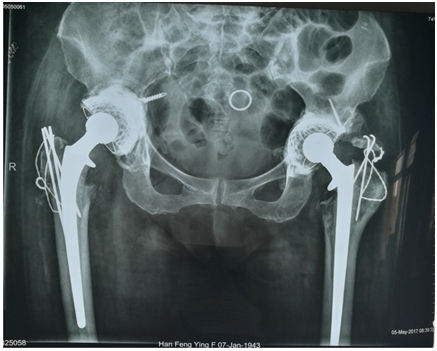

手术分期进行,2017年3月8日先进行了左侧翻修手术,手术顺利,术后病人恢复情况良好。5月2日再次对右侧进行了翻修手术,手术依然顺利完成。目前病人下肢等长,关节也不疼了,术后5天左右可以在家人的帮助下下地站立。